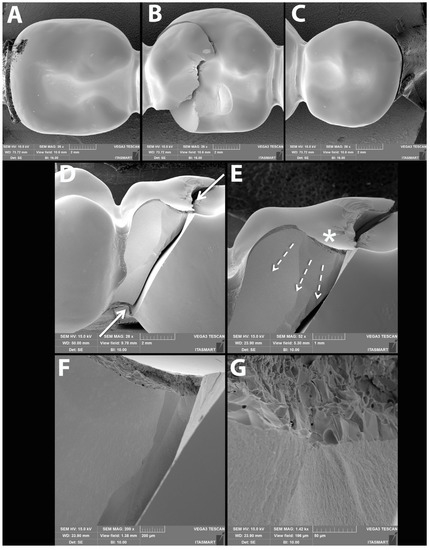

3.3. Failure and Fractographic Analysis after Single Load to Failure Testing

- The Rapid-Layer concept shifted failure modes from catastrophic bulk fractures to clinically repairable failures within the PICN veneer layer.

| Bulk fracture within connector | 10/10 (100%) | 10/10 (100%) | 10/10 (100%) | 10/10 (100%) | 8/10 (80%) | 10/10 (100%) | 3/10 (30%) | 1/10 (10%) |

| Bulk fracture without connector | - | - | - | - | 2/10 (20%) | - | - | - |

| Chipping | - | - | - | - | - | - | 7/10 (70%) | 9/10 (90%) |